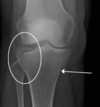

5

Intracapsular NOF

Subcapital fracture (intracapsular)